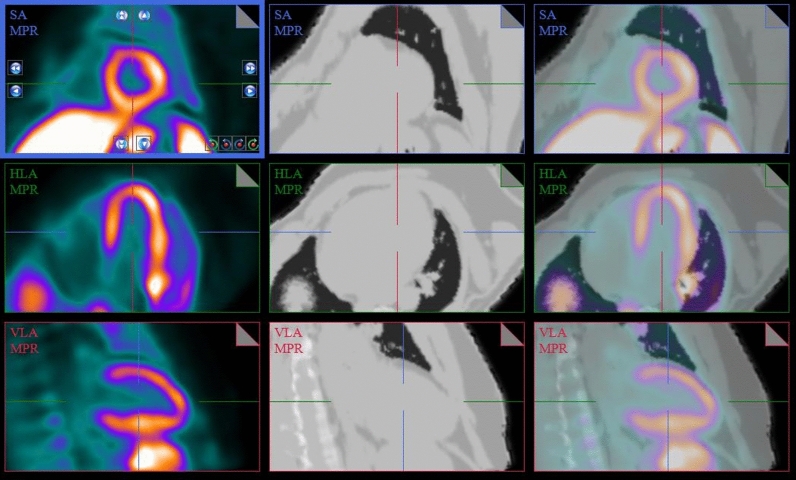

Figure 1.

Fusion of cardiac PET and MR-derived attenuation images of subject B shown in short axis (SA), horizontal long axis (HLA), and vertical long axis (VLA) views

Dynamic datasets (framing 9 × 10 s, 3 × 30 s, 2 × 60 s, 7 × 300 s) were reconstructed using the vendor supplied 3D OP-OSEM algorithm (3 iterations, 21 subsets) with corrections applied for normalization, dead-time, decay, scatter and random events. A 4-mm Hann smoothing was applied post-reconstruction. Images were corrected for attenuation using a mu-map derived from a breath-held Dixon MR image acquired pre-injection. The dynamic PET images were analyzed using FlowQuant version 2.4, which allows for both automatic and manual sampling along the vertical long, horizontal long, and short axes of the left ventricle (LV) myocardium (see Figure 1). The regional time activity curves from the left ventricle were fitted with three different models: Logan graphical, 1-tissue compartment (1-TCM), and 2-tissue compartment (2-TCM).